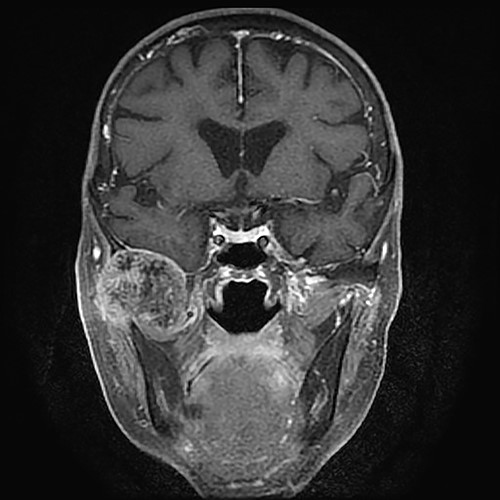

Gadolinium-enhanced T1-weighted magnetic resonance imaging showing the TMJ mass compressing the bottom of the right temporal lobe of the brain.

An 83-year-old woman was referred to our institution for treatment of right TMJ pain. She had first noticed the pain ~3 years earlier. The patient’s medical and family histories were unremarkable. Intra-oral examination revealed no abnormal findings associated with the right TMJ pain. Occlusal deviation was not observed. The maximum mouth opening was 28 mm, and transient pain occurred during mouth opening. A hard protrusion was observed in the right TMJ region. There was no evidence of cranial nerve paralysis or cervical lymphadenopathy. On T1- and T2-weighted magnetic resonance coronal images, the mass showed low signal intensity and compressed the bottom of the right temporal lobe of the brain. The mass about 35 mm in diameter was inhomogeneously enhanced by gadolinium (Fig. 1). The patient’s calcium, phosphate and uric acid concentrations were within the reference range.